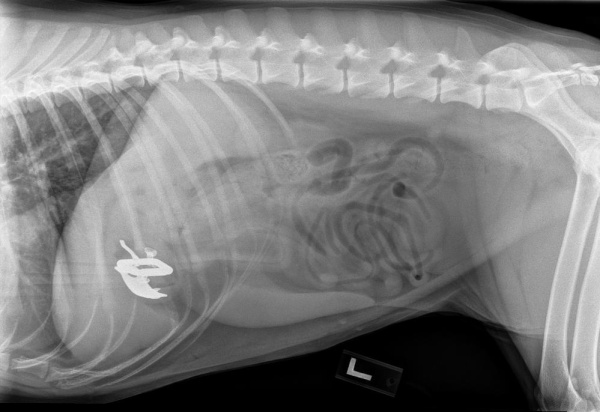

Radiographs play a critical role in diagnosing a wide range of conditions in pets. To ensure the highest quality imaging, we utilize state-of-the-art digital X-ray equipment and have extensively trained our technicians in advanced radiographic techniques.